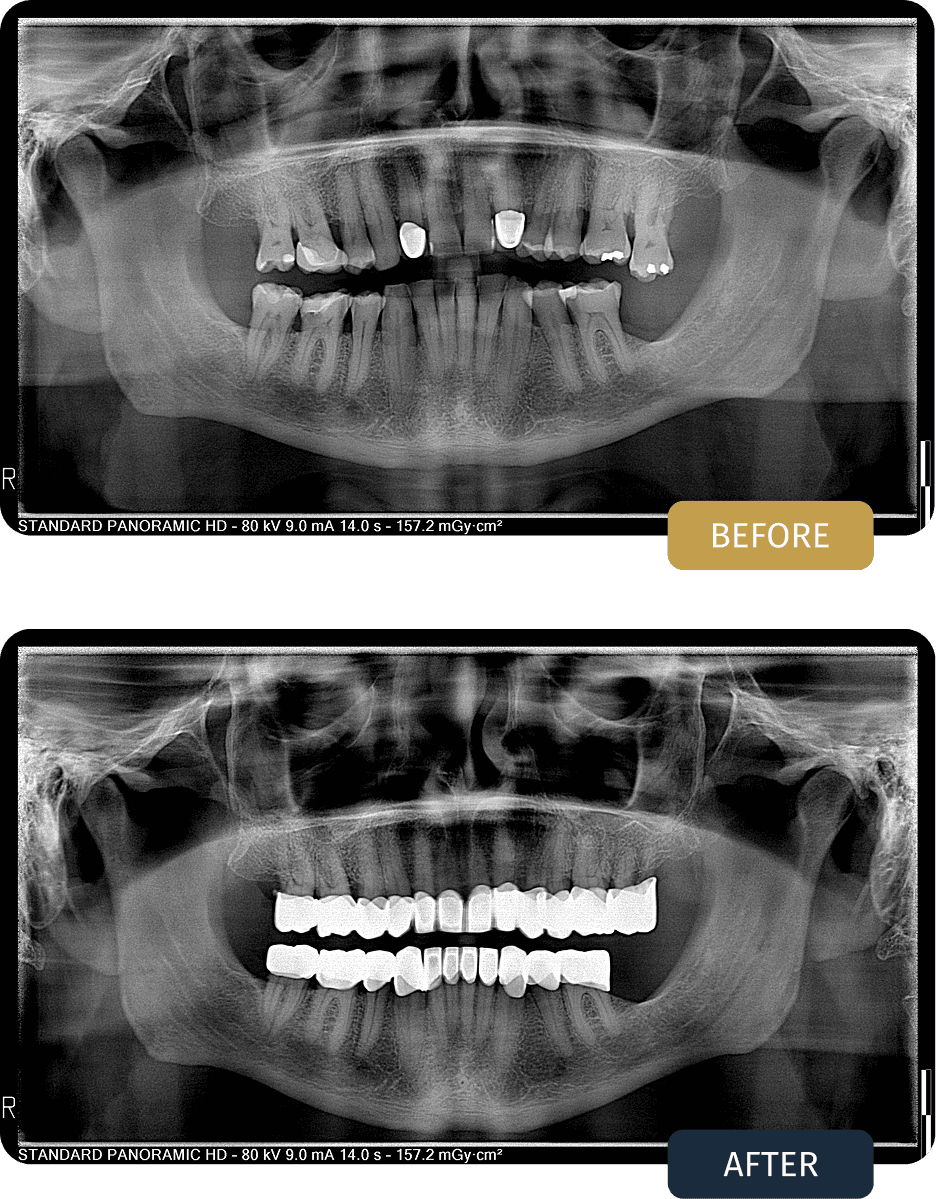

John Kelly, 65, from London

Treatment Type

• 23 Crowns

• 2 Fillings

Twenty three crowns were placed to reinforce weakened teeth, restore proper chewing surfaces, and improve overall bite harmony. In addition, two fillings were carried out to address localized decay and preserve natural tooth structure where possible.

BEFORE

John presented with multiple worn and damaged teeth, alongside older restorations that were no longer providing reliable function or protection.

Panoramic examination showed the need for comprehensive restorative treatment to stabilise the bite, protect remaining tooth structure, and improve long term oral function without the need for surgical intervention.

AFTER

Post treatment panoramic imaging confirmed well seated crowns with balanced bite alignment and stable restorations.

The final result provided John with improved chewing comfort, enhanced dental stability, and a durable outcome designed to support everyday use and long term oral health.